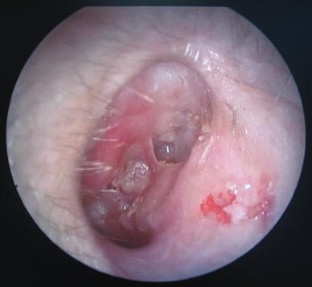

Fig. 3